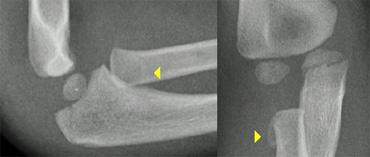

Gãy lồi cầu ngoài (3).

Chẩn đoán gãy lồi cầu ngoài có thể là một thách thức.

Đường gãy đôi khi hầu như không nhìn thấy được (hình).

Ghi nhớ rằng gãy lồi cầu ngoài là loại gãy xương khuỷu tay phổ biến thứ hai ở trẻ em và biết được vị trí cần tìm kiếm sẽ giúp ích cho bạn

Lateral condyle fracture. On the x-ray only a small metaphyseal fragment is visible. The detatched fragment however is larger than it appears on the radiograph. The fracture extents into the lateral ridge of the trochlea. Elbow is probably unstable.

LEFT a subtle lateral condyle fracture. Less than 2 mm displacement and probably stable. RIGHT a different case. Oblique view gives nice impression of fracture. Blue arrow indicates a cleft epiphysis of the radius (normal variant)

Gãy lồi cầu ngoài (5)

Trong gãy lồi cầu ngoài, đường gãy thực sự có thể rất khó nhận thấy vì mảnh xương vùng hành xương có thể rất nhỏ.

Mảnh gãy thường bị xoay.

Tư thế chụp chếch có thể hữu ích, nhưng thường không được thực hiện thường quy (hình).

Two cases of overprojection of the capitellum on humeral epiphysis simulating a fracture. Notice olecranon fracture on the right

Gãy lồi cầu ngoài (6).

Hình ảnh lồi cầu xương cánh tay nhô ra quá mức trên phần hành xương cánh tay có thể giả dạng gãy lồi cầu ngoài (hình).